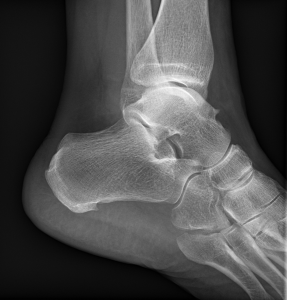

Princip vyšetření je založen na schopnosti rentgenového záření pronikat hmotou a dle vlastností jednotlivých tkání se specificky zeslabovat. Výsledkem je obraz zachycený na citlivý materiál – rentgenový film či detekční systém přístroje. Rentgenové vyšetření se hodí zejména k posouzení kostí a plic. Dále je možné např. z obsahu plynu ve střevech posoudit průchodnost střeva. Na snímcích lze hledat cizí kovová tělesa v těle.

Provádíme kompletní spektrum základních i speciálních skiagrafických vyšetření skeletu i měkkých částí lidského těla.

Ukázky RTG snímků